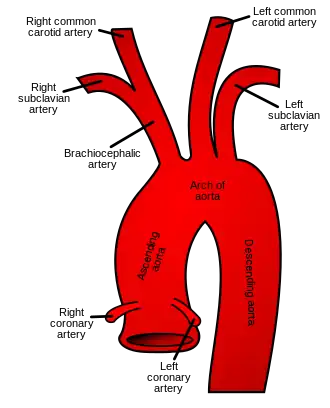

The common carotid artery arises directly from the aorta on the left and as a branch of the brachiocephalic trunk on the right. | |

In anatomy, the left and right common carotid arteries (carotids) (English: /kəˈrɒtɪd/[1][2]) are arteries that supply the head and neck with oxygenated blood; they divide in the neck to form the external and internal carotid arteries.[3][4]

The common carotid arteries are present on the left and right sides of the body. These arteries originate from different arteries but follow symmetrical courses. The right common carotid originates in the neck from the brachiocephalic trunk; the left from the aortic arch in the thorax. These split into the external and internal carotid arteries at the upper border of the thyroid cartilage, at around the level of the fourth cervical vertebra.

Only the left common carotid artery has a substantial presence in the thorax. It originates directly from the aortic arch, and travels upward through the superior mediastinum to the level of the left sternoclavicular joint.